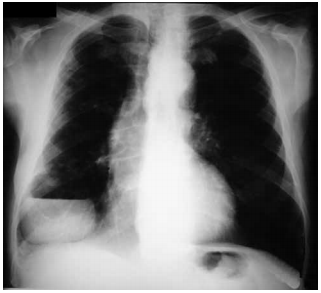

Paciente de 66 anos, sexo masculino, chega ao ambulatório relatando quadro de tosse, expectoração amarelada e febre (39 ºC) há 2 dias, acompanhada de dor torácica. Ele também refere etilismo e tem dentes em mal estado de conservação. Ele satura 91% em ar ambiente e a frequência respiratória encontra-se em 28 ipm. A seguir o raio X de tórax.

enunciado 601331-1

Neste momento, a conduta correta a ser instituída é